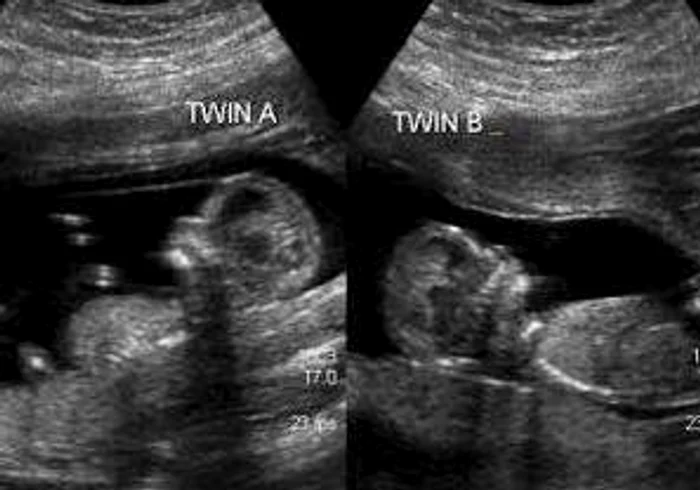

Mamă a doi copii, un băieţel pe nume Cezar (8 ani) şi a unei fetiţe, Iulia (6 ani) Adriana Iovi Stere a anunţat pe pagina ei de Facebook că este însărcinată cu gemeni. Ea a publicat pe reţeaua de socializare şi o imagine cu ecografia.

"It's a boy!" Si acum, Cezar, Iulia, Vali... repetati! E ok, asta e varianta finală!", a scris tânăra mămică.